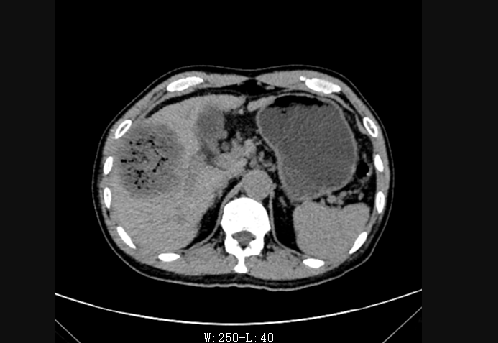

术前

术后